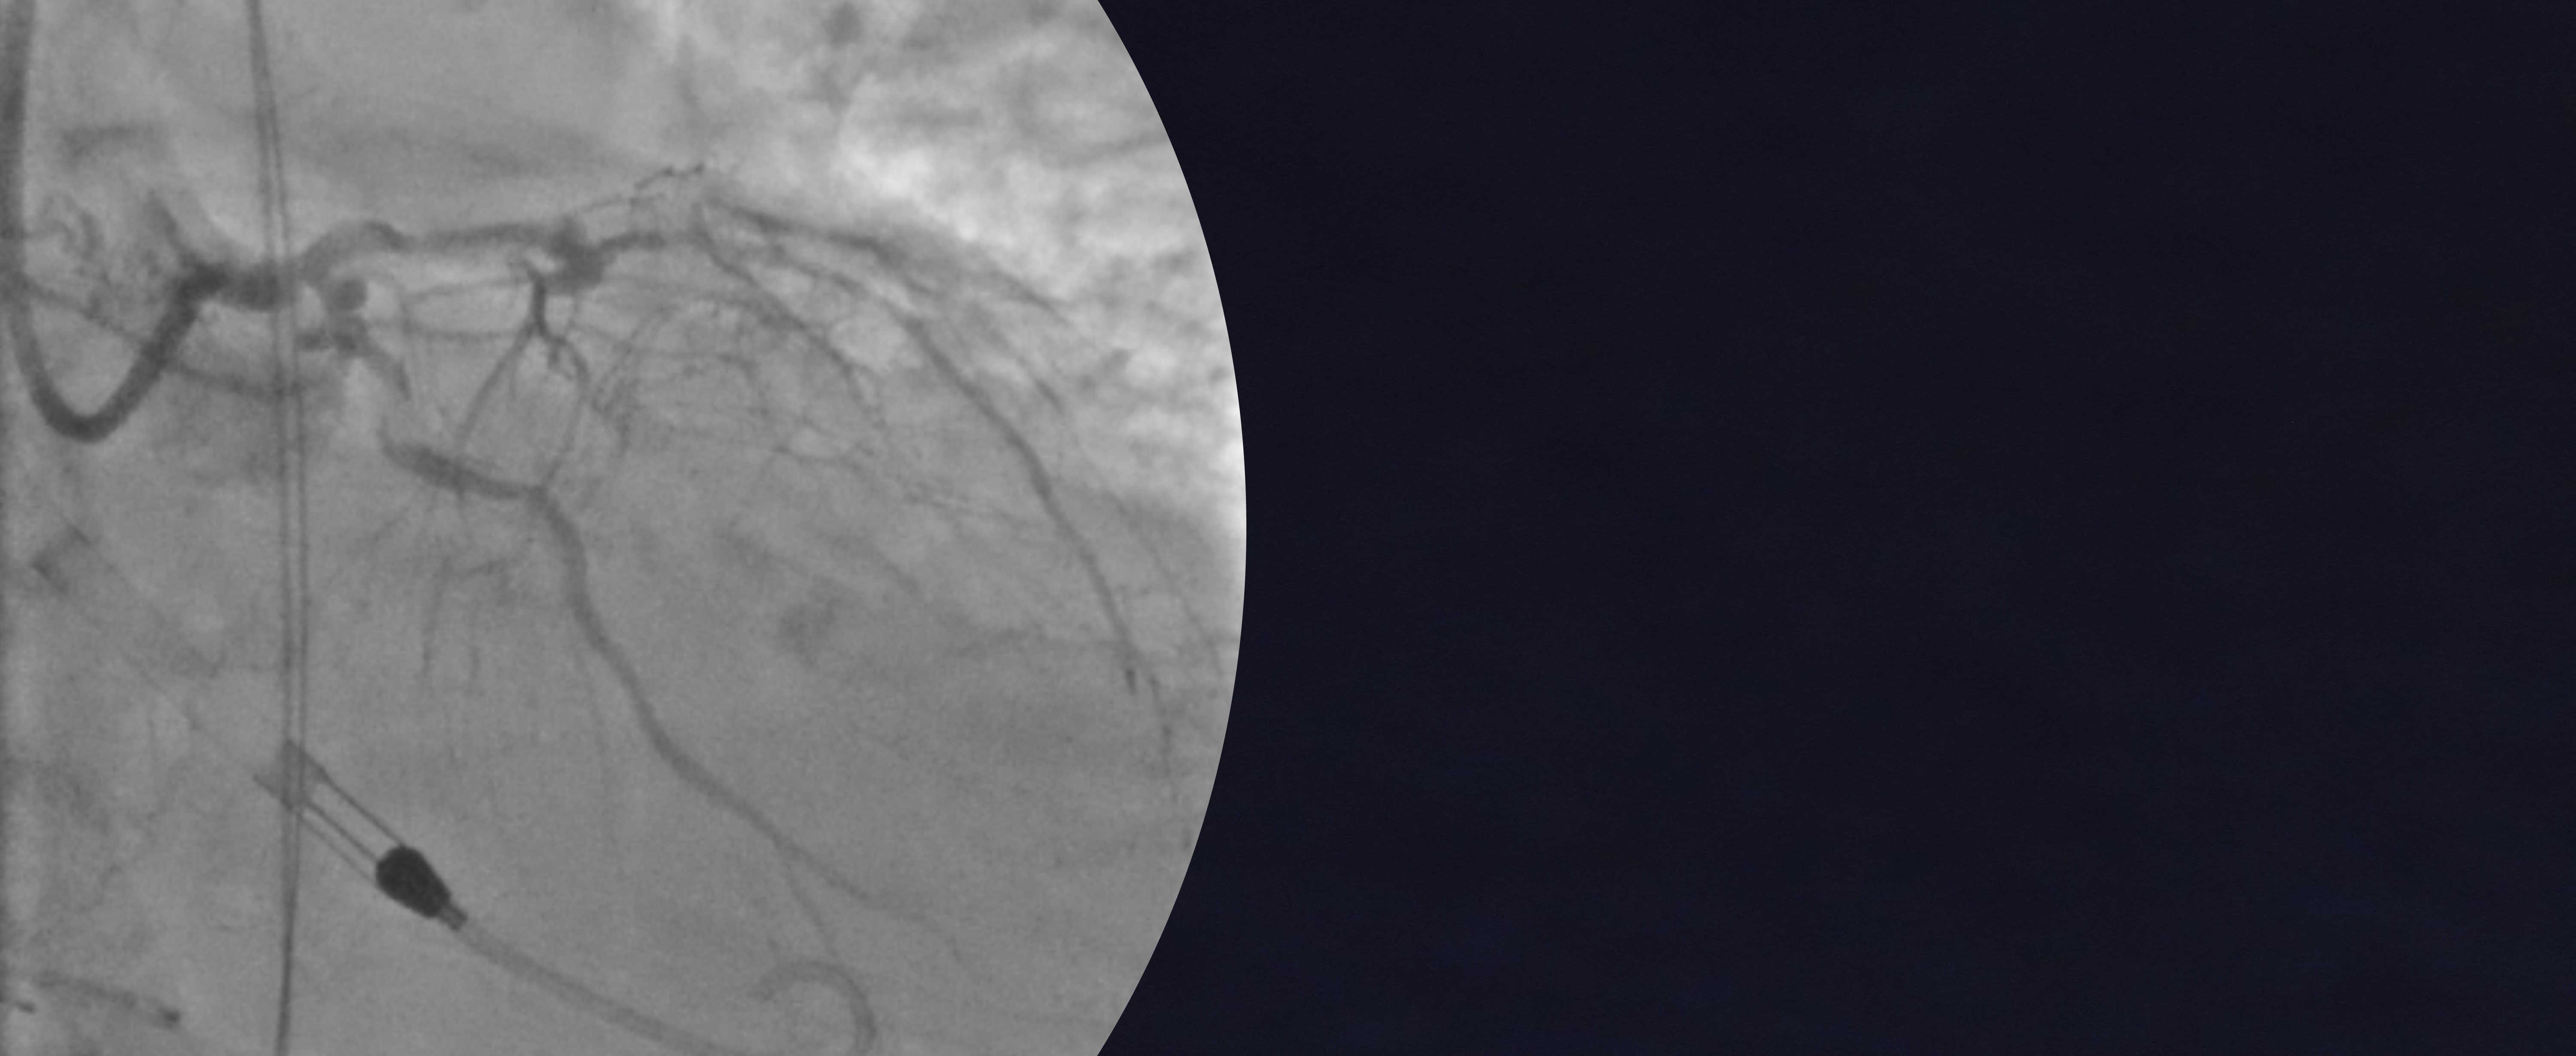

The BCIS myocardial Jeopardy Score describes the amount of myocardium at risk due to severe coronary stenoses.

It accounts for left main stem disease and coronary artery bypass grafts, and predicts mortality after PCI.